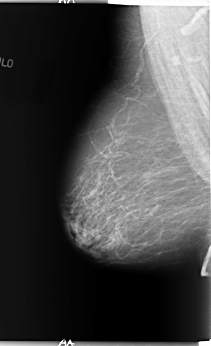

B_3089_1.RIGHT_MLO

RIGHT_MLO LINES 5880 PIXELS_PER_LINE 3576 BITS_PER_PIXEL 12 RESOLUTION 50 NON_OVERLAY